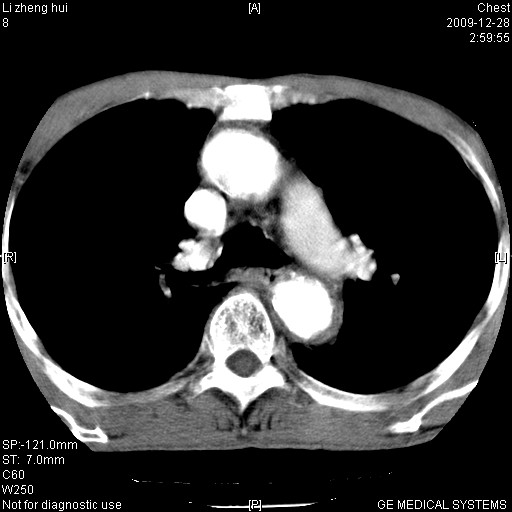

男  79岁 胸部痛急诊入院,晚上做的增强

考虑主动脉瘤?(增粗、钙化、壁血栓?)

支持降主动脉瘤,不考虑夹层

动脉瘤伴附壁血栓

1)考虑胸主动脉壁间血肿或夹层动脉瘤。2)多发性肝囊肿。

1)考虑胸主动脉附壁血栓或夹层动脉瘤。2)多发性肝囊肿。

考虑大动脉炎,附壁血栓形成。